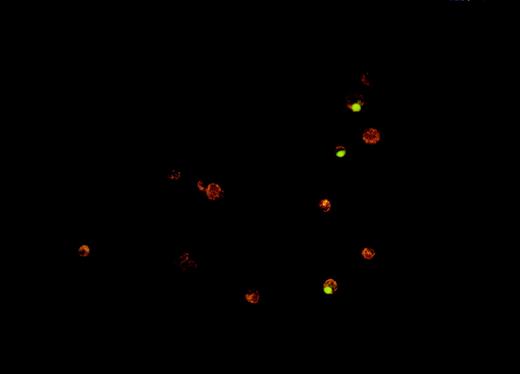

VP-16 kills Burkitt lymphoma cells almost entirely by inducing apoptosis, and this mode of cell death is inhibited by the presence of H2O2.16 Cells treated either with H2O2 alone or with VP-16 in the presence of H2O2 are mostly nonapoptotic, showing cytoplasmic swelling, mild pyknosis of the nucleus, and little or no DNA fragmentation, caspase activation, or annexin-V binding.16 Because these cells resemble necrotic cells except for the pyknosis of the nucleus, they are referred to as pyknotic/necrotic. Using cell morphology as the criterion for assessing the mode of cell death, we quantified cell death by fluorescence microscopy after staining the cells with the nuclear dyes Hoechst 33342 and PI. This method allowed us to distinguish apoptotic from nonapoptotic cells and also revealed whether the cells had lost their plasma-membrane permeability barrier (see “Materials and methods”). Examples of the different cell death morphologies identified with this method are shown in Figure1.

Morphologies of live and dead Burkitt lymphoma cells as determined by fluorescence microscopy.

JLP 119 cells were treated with 50 μmol/L H2O2. Cells were harvested after 22 hours, stained with Hoechst 33342 and PI, and examined by fluorescence microscopy as described in “Materials and methods.” Characteristic live and dead cell morphologies are identified by the arrows as follows: double arrow, live cell; long thin arrow, necrotic cell; long fat arrows, pyknotic/necrotic cells; short white arrow, membrane-permeable apoptotic cells; short open arrow, membrane-intact apoptotic cell.